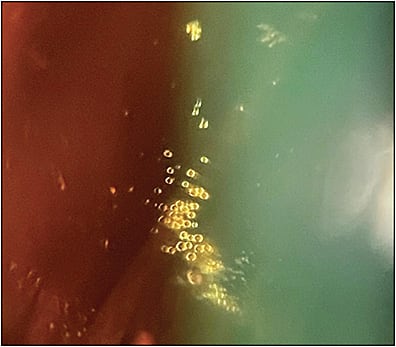

Retina specialists have been aware that deposits of silicone oil can be observed following IVIs, leading researchers to investigate more thoroughly. A cross-sectional, comparative study was done in 2019 examining the prevalence of silicone oil droplets in the vitreous of patients who had undergone IVI procedures compared to patients who had not. Using ultrasonography, silicone oil droplets were found in the eyes of 76% of patients who had received treatment and found in only 3% of patients that had not received any treatment.2

Silicone oil droplets may build up over time, especially in those patients who have received many injections in the past. The presence of these intravitreal droplets following injections may cause patients to experience floaters in their vision. Floaters have been shown to negatively impact patient quality of life and are perceived by many to be a significant health problem. Evidence of the impact that these side effects have on patient wellbeing was put on display in the 2018 ASRS PAT Survey, which found that among ophthalmologists in the United States who had performed bevacizumab (Avastin; Genentech) IVIs that year, 1.8% had at least 1 patient seek legal action because of intraocular silicone oil. The survey also found that 5.2% of ophthalmologists that year performed at least 1 vitrectomy to treat symptomatic floaters produced by silicone oil.3 These potentially preventable vitrectomies come with risks, such as retinal detachment, vitreous hemorrhage, and endophthalmitis, all of which can result in loss of vision.